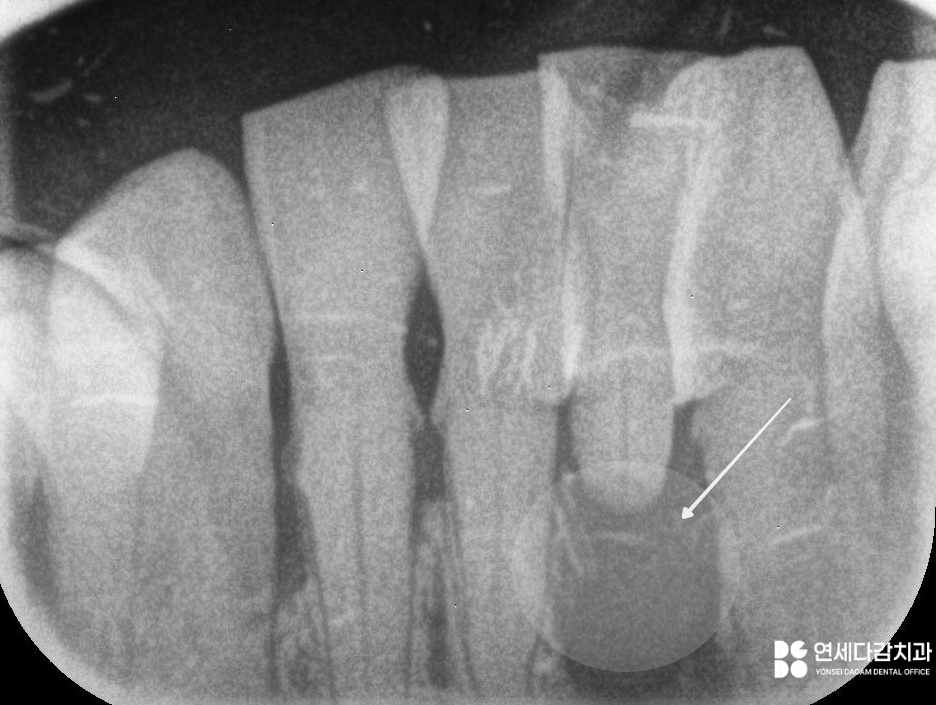

그러나 치주 질환의 주된 원인이 되는

치석이 잇몸 하방으로 내려가게 되면

치주염으로 발전하게 됩니다.

이때는 치석이 독소 같은 작용을 하면서

치조골을 녹이는 문제를 일으킬 수 있습니다.

결국 치근을 제대로 잡아주지 못해

치아는 버틸 힘을 잃고 흔들리기 시작합니다.

심한 경우 외상이나 사고가 없더라도

자연스럽게 탈락하는 문제로 이어집니다.

이러한 변화를 방지하기 위한 방법 중 하나가

바로 '잠간 고정술'입니다.

이는 탈락한 부위 주변 환경을 고려해

간단한 레진 등의 재료를 이용하여

임시로 메워주는 방법으로 진행됩니다.

다만, 개롱역 치과 에서 보여드리는 것과 같은

발치된 치아를 이용한 방식 같은 경우

일반적인 방법과는 다릅니다.

보통 흔들리는 곳과 그렇지 않은 치아를

서로 접착하면 유지력을 잃게 될 수 있습니다.

이 경우 환자분께서 발거치아를

꼭 다시 붙이시길 원하셨습니다.

환자분이 충분한 설명을 이해하고

사용에 제한을 두는 조건으로 처치를 원할 경우

예외적으로 시행되기도 합니다.

잠깐 고정술은 어디까지나

앞으로의 치료 전까지 유지하기 위한

임시 대안이라는 것을 이해하셔야 됩니다.